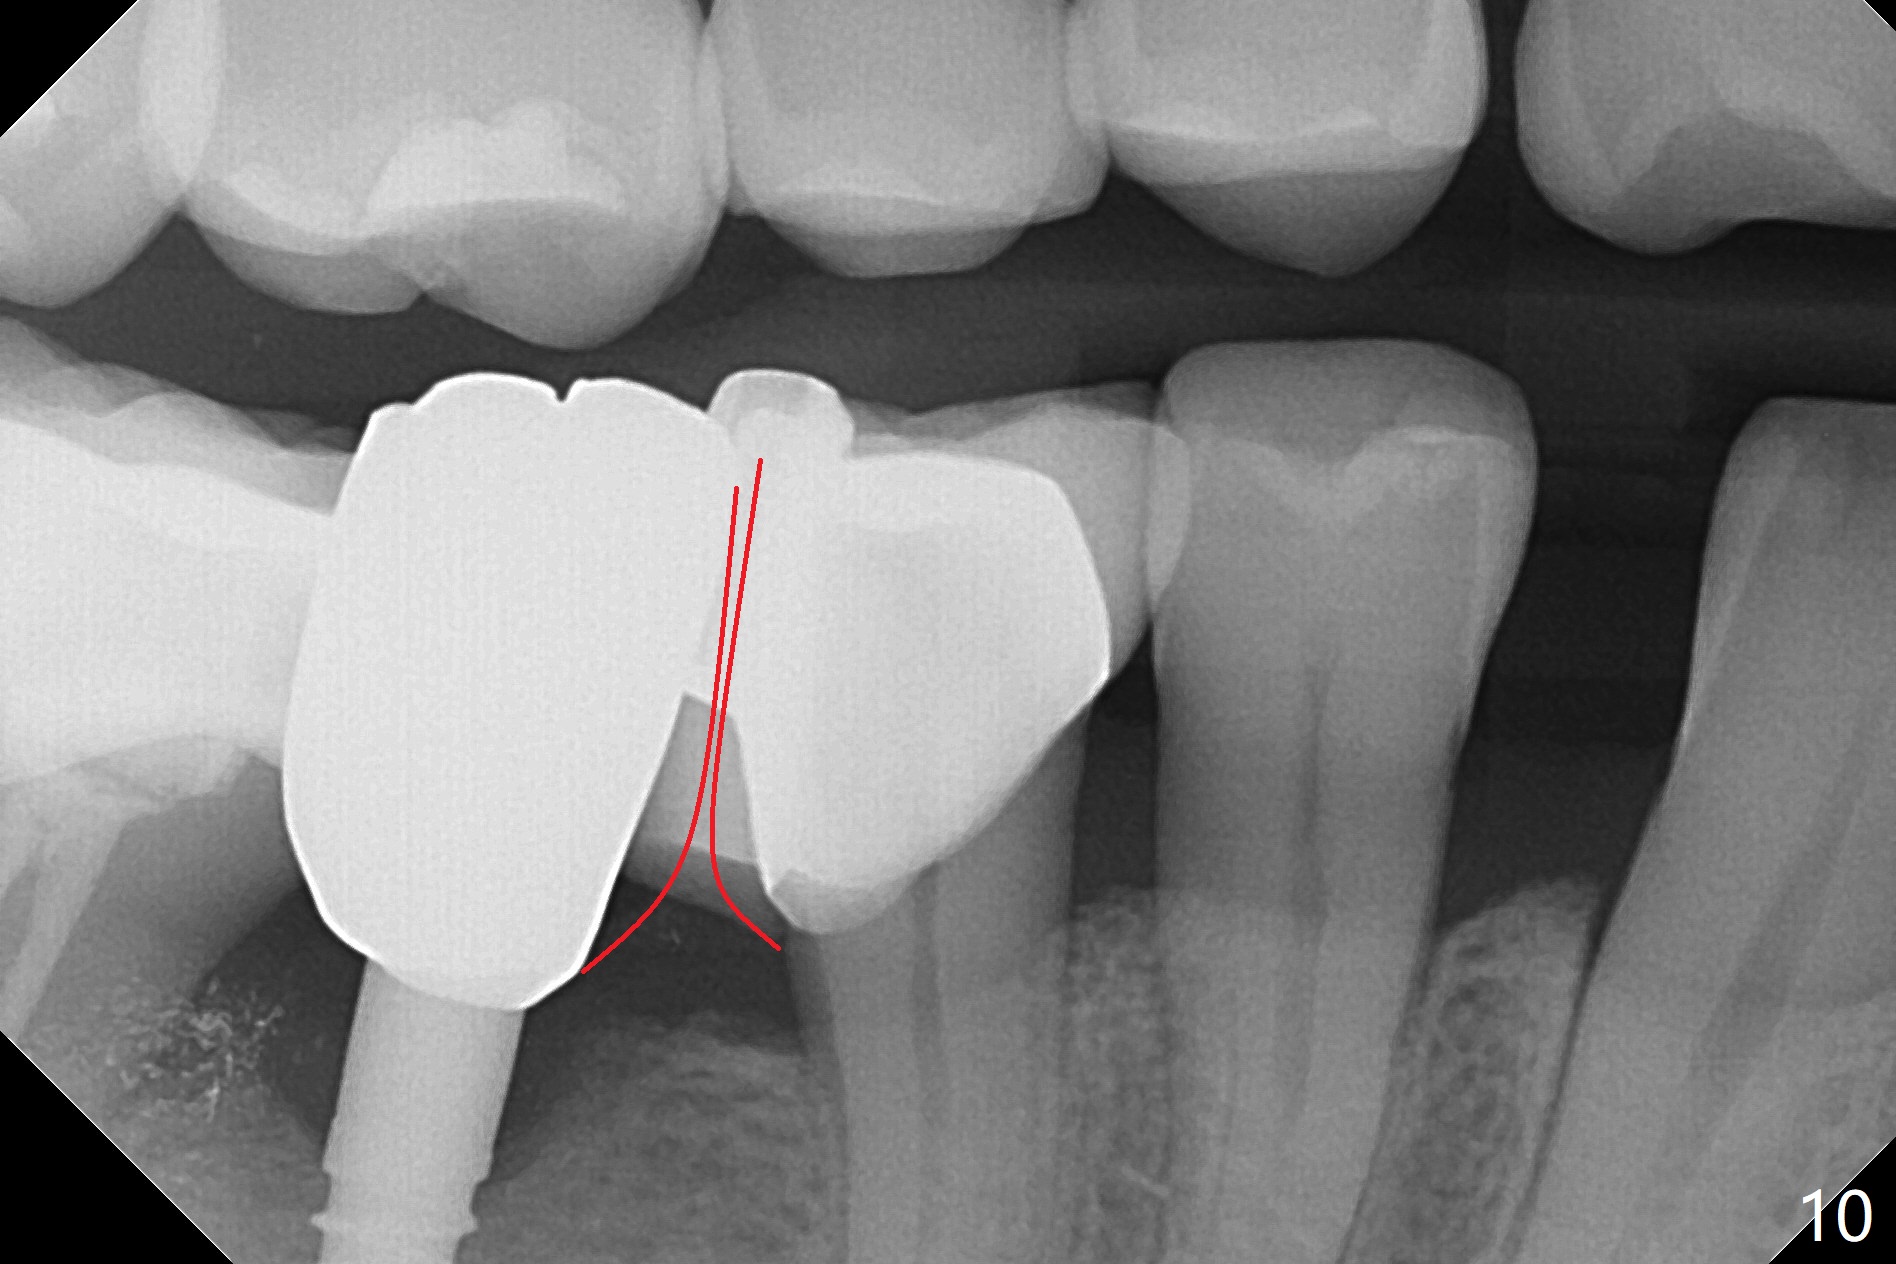

There is a space underneath the pontic at #30 (Fig.1 *), the basis for food impaction. After sectioning between the pontic and the posterior retainer, the pontic is removed from the anterior retainer with an attachment (Fig.2 *). The initial depth of osteotomy is 10 mm following ridge top reduction (Fig.3). A 3x10(4) mm 1-piece implant is placed with >50 Ncm; to reduce possibility of crown dislodgement from the implant, the retainers will be kept with modification of the proximal surfaces as shown by curved lines in Fig.4. Periodontal dressing is applied after suturing. There is no postop paresthesia. The periodontal dressing remains in place 2 weeks postop because of engagement into the attachment slot and undercuts (Fig.5). The patient returns 3 months postop; after minor contour adjustment (Fig.6 red curved line), impression is taken. The permanent crown is temporarily cemented (3.5 months postop) in case of food impaction due to the distal overhang of the tooth #29 (Fig.7). In fact the patient returns 4.5 months post cementation with right TMD (muscle relaxant prescribed) and food impaction, although there is no bone resorption (Fig.8,9). It appears that the crown at #29 needs to be redone, while porcelain will be added to the mesial surface of the one at #30 (Fig.10 red lines). In fact the crown at #30 is redone because of loose proximal contact with #31; there is no bone resorption 13 months post cementation (Fig.11). Bone resorption remains unnoticeable 28 months post cementation (Fig.12,13).